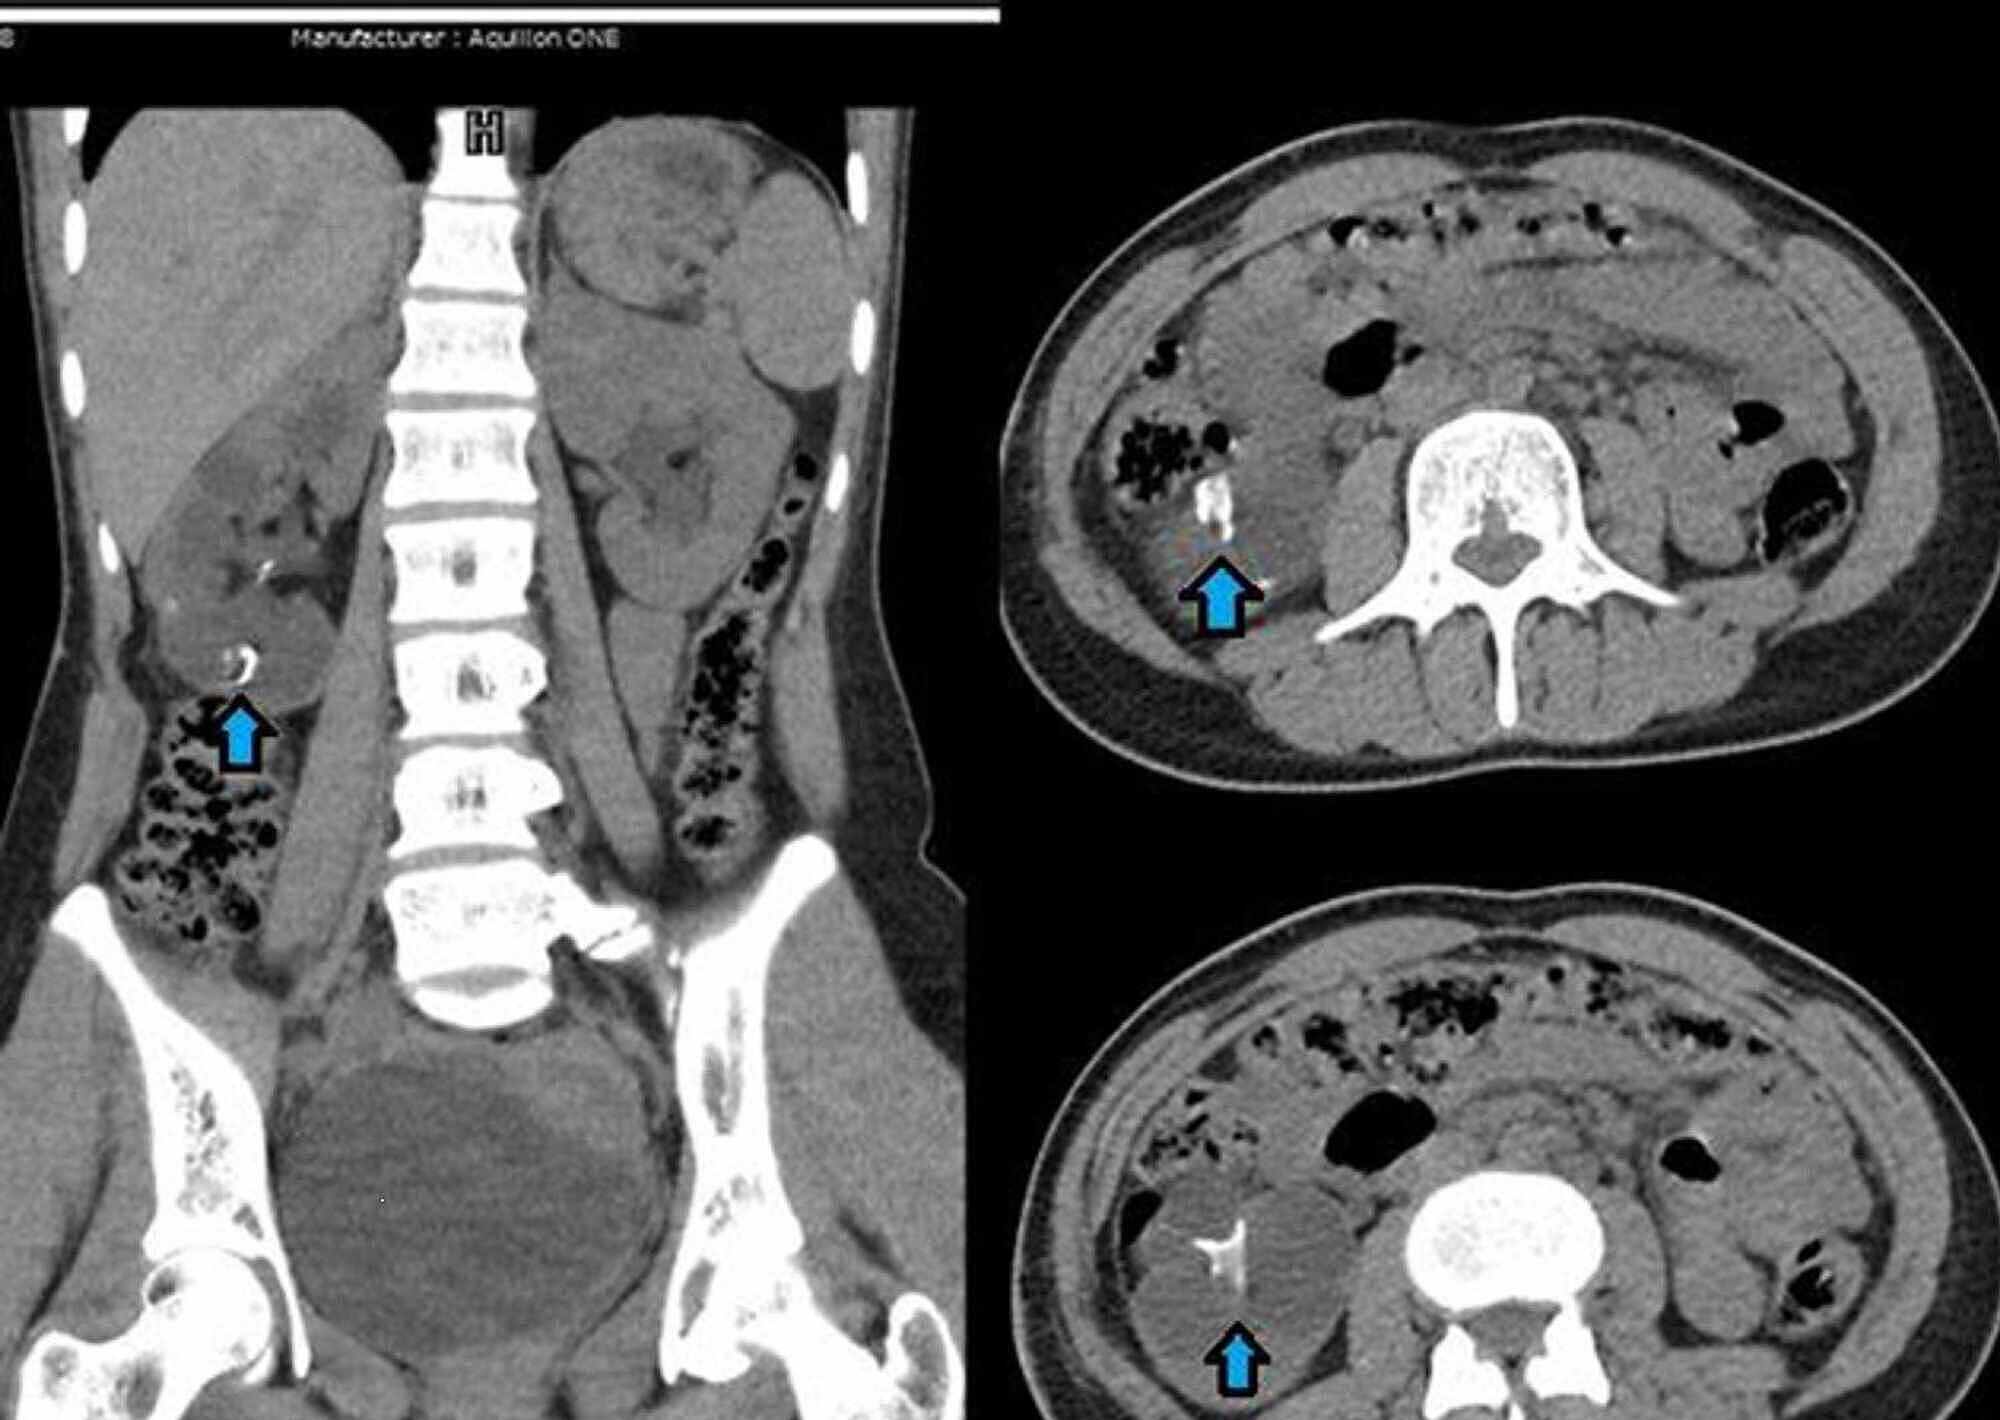

Noncontrast CT in the Evaluation of Urinary Tract Stone Obstruction Ct Scan Kidney Stone Protocol Learn why your provider might order a scan. Patients may present with the. If allergic to contrast or poor. Scan from top of kidneys to bottom of symphysis pubis. Learn about the procedure, reasons, risks, and preparation for a ct scan of the kidney, which can detect kidney stones and other conditions. Is a ct scan necessary to diagnose kidney. Ct Scan Kidney Stone Protocol.

Radiodiagnosis Imaging is AmazingInteresting cases Renal calculus Ct Scan Kidney Stone Protocol Scan from top of kidneys to bottom of symphysis pubis. Not all cases require imaging tests. R/o kidney or ureteral stones. Kidney stone disease (nephrolithiasis) is a common problem in primary care practice. Learn why your provider might order a scan. Patients may present with the. Is a ct scan necessary to diagnose kidney stones? If allergic to contrast or. Ct Scan Kidney Stone Protocol.

Radiodiagnosis Imaging is AmazingInteresting cases Ureteric Ct Scan Kidney Stone Protocol Patients may present with the. R/o kidney or ureteral stones. If allergic to contrast or poor. Learn about the procedure, reasons, risks, and preparation for a ct scan of the kidney, which can detect kidney stones and other conditions. Learn why your provider might order a scan. Scan from top of kidneys to bottom of symphysis pubis. Kidney stone disease. Ct Scan Kidney Stone Protocol.